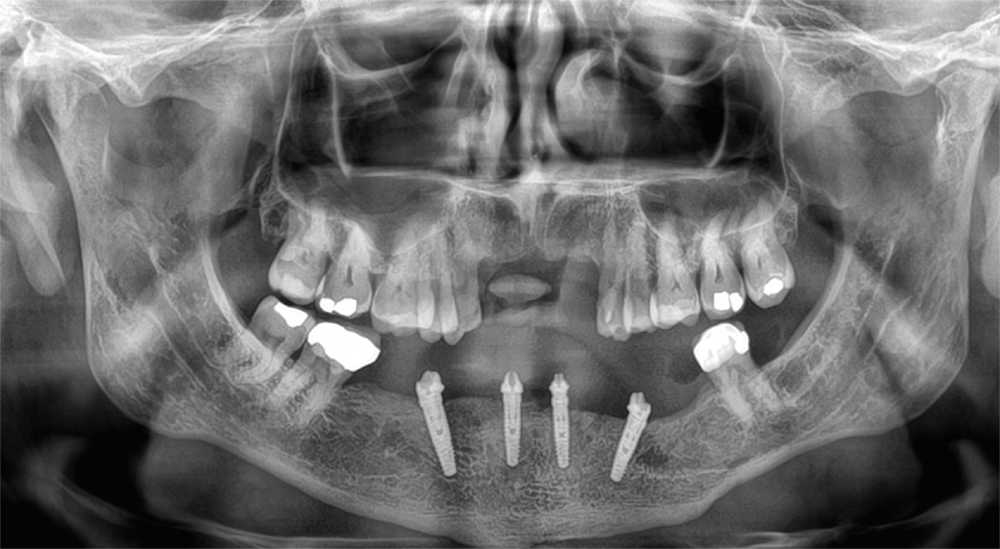

Kirk’s X-Rays Before and After

Before surgery, his partial denture not only fit poorly but was also contributing to bone loss around his anterior teeth. This type of bone loss can make removable prostheses even less stable over time.

With All-on-4 dental implants, that concern was eliminated. The x-rays show how four strategically placed implants now provide a strong, lasting foundation for his full arch of teeth. Instead of relying on a removable denture, Kirk has a stable solution designed to protect his jawbone and restore function.